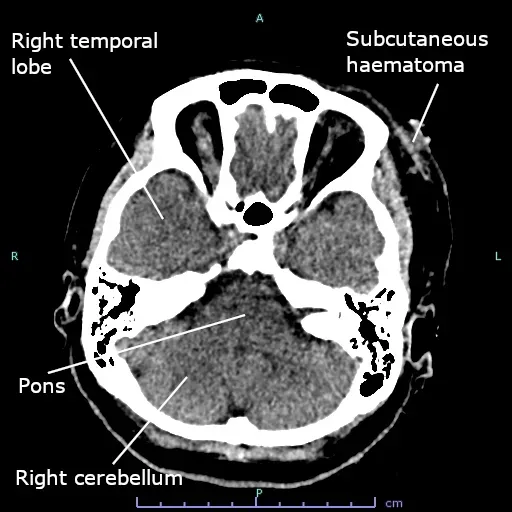

One of the most unsettling hints that consciousness behaves differently from standard biology comes from patients whose brains look catastrophically damaged yet remain eerily lucid. In several reported cases, people living ordinary working lives were found, after scans for unrelated issues, to have vastly reduced brain tissue, with the remaining cortex squeezed into a thin outer shell. Evolution would suggest that losing that much neural hardware should erase the self, but in these people, personality and memory seemed surprisingly intact. It is as if you removed most of a computer’s components and the operating system just shrugged and kept running. Stories like these do not prove the brain is unnecessary, but they do suggest we may not fully understand which parts of it are truly doing the heavy lifting.